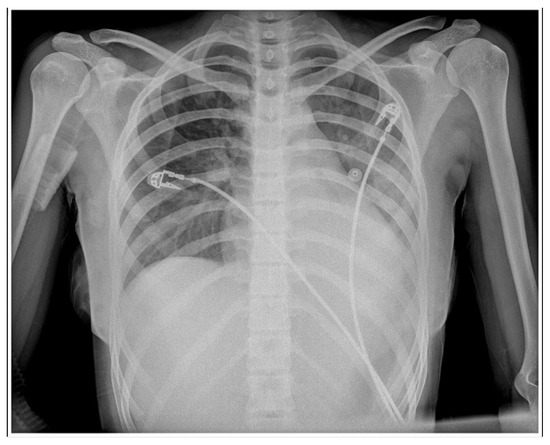

Case Report